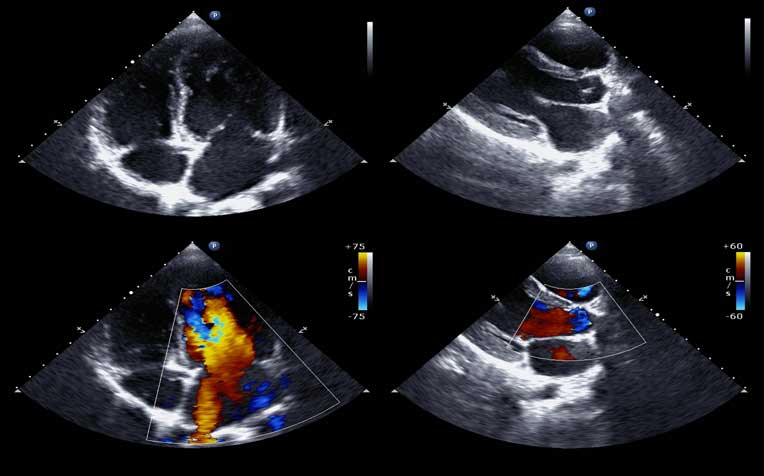

The Stress Echocardiogram captures images of the heart at its peak heart rate.

This test adds on to the stress test by including an imaging test precodure called echocardiography. Images of the heart are taken while the patient is performing the stress test or while lying down immediately after reaching peak exercise level. It captures images of the heart at its peak heart rate.

It uses ultrasound to study how the heart contracts and pumps blood while under stress. It also measures the size and function of the heart’s chambers, the motion of the heart valves, and the way blood is flowing. There are two kinds of stress tests. The pharmacological stress echocardiogram is for patients who are unable to exercise. The exercise stress echocardiogram is for those who can carry out treadmill exercises.